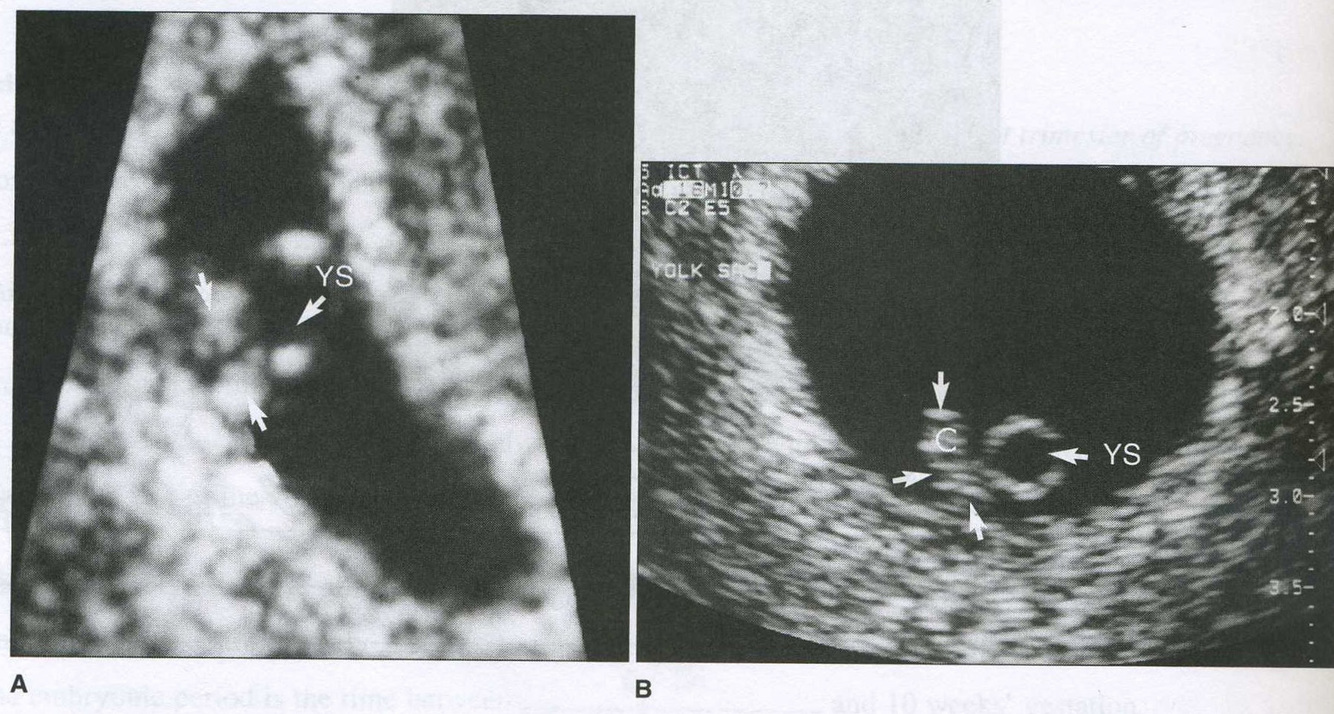

identify the structure that the arrows are pointing to in this 6 week gestation

decidua capsularis

identify the disklike structure adjacent to the yolk sac in image A

identify wha the letter “C” represents in image B

5 1/2 week embryo

embryonic cranium